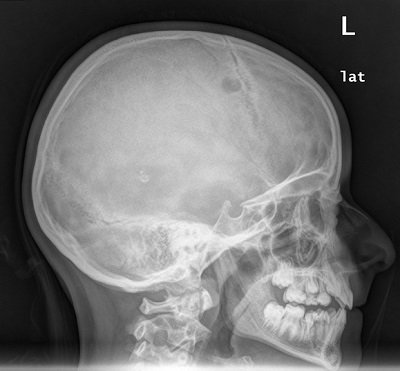

El segundo caso corresponde a una niña de 10 años que acude a urgencias por aparición de una tumoración dolorosa a nivel parietal de siete días de evolución sin antecedente de traumatismo previo. En la exploración se palpa una tumefacción 2×2 en región frontotemporal derecha, de consistencia blanda, dolorosa a la palpación, sin eritema, calor o rubor. Se realiza una radiografía craneal en la que se objetiva una lesión osteolítica en porción anterior hueso temporal derecho, sugestiva de HCL ósea monostótica (Fig. 2). Tras este primer diagnóstico de presunción se realiza TAC craneal y estudio de extensión (ecografía abdominal, radiografía de tórax, serie ósea, gammagrafía ósea) en donde no se evidencia afectación a distancia. Se procede a la exéresis quirúrgica por parte del servicio de neurocirugía, con confirmación anatomopatológica de HCL ósea.

| Figura 2. Radiografía craneal en la que se objetiva una lesión osteolítica en porción anterior hueso temporal derecho, sugestiva de HCL ósea monostótica |